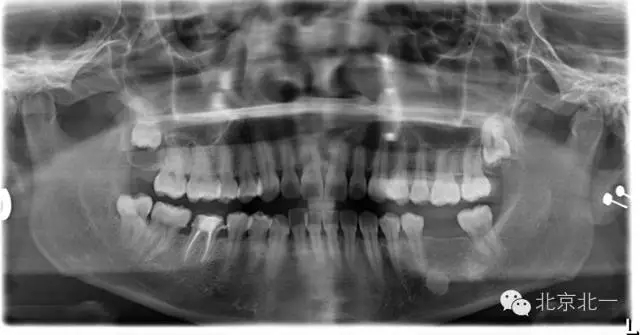

先看一例病例。頜骨內(nèi)單發(fā)高密度影像。是什么?能不能影響種植, 骨島是什么鬼?需要怎么處理?

【CBCT表現(xiàn)】:發(fā)生致命性骨炎的環(huán)亞暢游牙體病變,其CBCT表現(xiàn)為圍繞根尖的骨質(zhì)密度增高區(qū),骨小梁增多增粗,骨髓腔變窄甚至消失,與正常骨組織分界不明顯。根尖部牙周膜間隙可增寬,根尖無增粗膨大。

根尖片顯示D6深齲,根尖低密度區(qū)周圍骨小梁增粗、增多,骨質(zhì)密度增高,骨髓腔變?。ê谏^)。

主要和根尖型骨島鑒別,主要集中位于根尖區(qū)的骨島,

【CBCT表現(xiàn)】:

在CBCT上,根尖型骨島無低密度帶狀影包繞,與周圍骨質(zhì)分界清晰,具有特征性的毛刷樣邊緣,且其發(fā)生區(qū)域的牙根牙周膜影像連續(xù)、完整、不導(dǎo)致頜骨的膨隆。

右下頜C4根尖區(qū)課件一類圓形高密度影,與周圍骨質(zhì)分界清晰,C4牙周膜影像連續(xù)、完整,下頜骨未見膨隆。